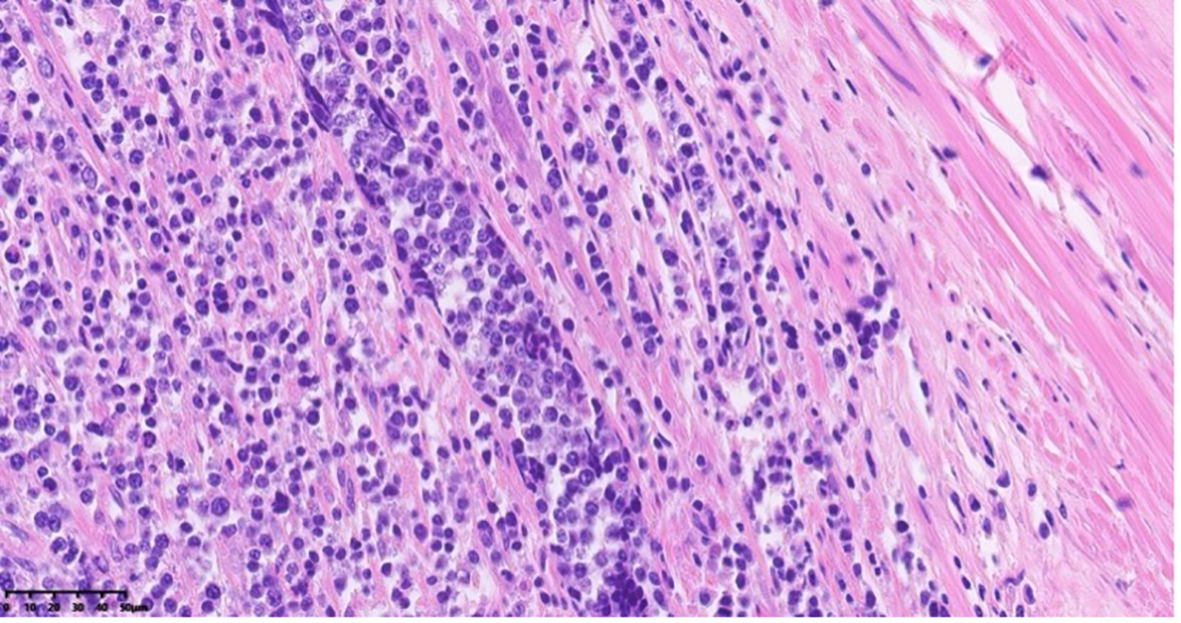

The appendix specimen measured 9 cm in length and 0.8 to 1.9 cm in diameter. (Figure 3) The serosal surface was mildly congested with slight fibrinous adhesions. The wall structure remained intact, and the blind end was dilated and thickened, measuring 5 cm in length and 1.9 cm in diameter. The cut surface was porcelain white. Histopathological examination revealed lymphoma involving the tip and part of the body of the appendix. The surgical margins were negative, with no evidence of tumor infiltration at the resection edges. Further analysis (Figure 4) demonstrated diffuse B-cell lymphocytic infiltration throughout the full thickness of the appendiceal wall, consistent with a diagnosis of non-Hodgkin lymphoma, most likely high-grade B-cell lymphoma.

Figure 4

Histopathological section of appendiceal tissue with H&E staining under 40x objective lens magnification using light microscopy.

Histopathologically, DLBCL is characterized by large, pleomorphic cells with prominent nucleoli and a high mitotic rate. These cells infiltrate the tissue in a diffuse pattern, and the tumor may involve the full thickness of the organ wall. In primary appendiceal DLBCL, the appendix becomes significantly enlarged and may exhibit signs of perforation, with the tumor potentially extending to adjacent tissues such as mesenteric fat or the peritoneal cavity.